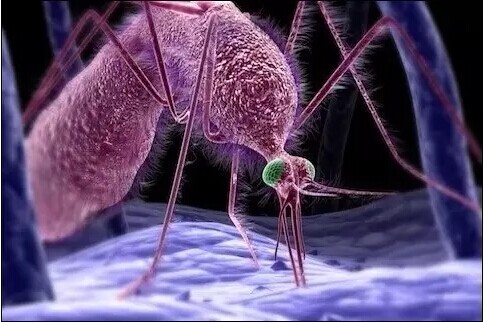

蚊子在人体皮肤表面吸血

蚊子吸血过程